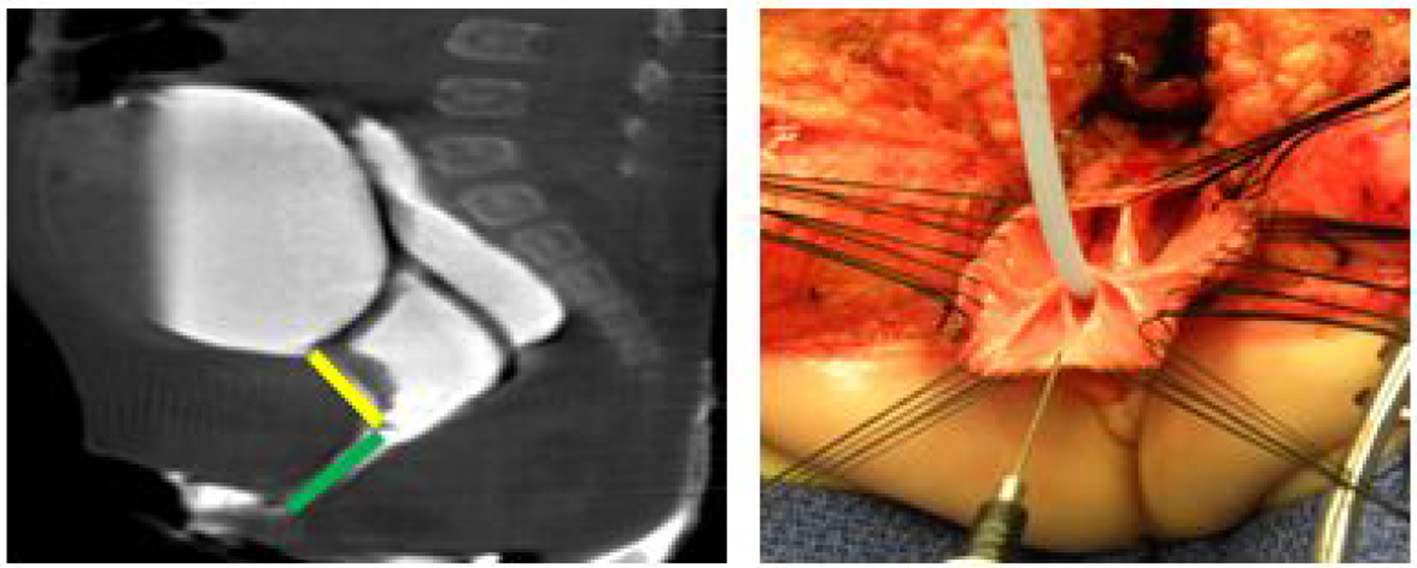

(2) The description of the technique of the TUM has been previously reported and the technique we employ does not differ from this approach (4). The surgery is started with mapping of the anal sphincter. In this instance a full posterior sagittal incision will be required. The incision is carried from the coccyx to the common channel and the common channel is opened posteriorly until the rectum and vagina/s are visible. The rectum is then mobilized in the same way as described above. Thereafter sutures are placed in the edge of the urogenital complex and the entire structure is mobilized in a full thickness fashion without compromising the integrity of the wall (Figure 2). The tissue is divided 5 mm posterior to the clitoris to allow for the urethroplasty to be placed directly posterior to the clitoris in a visible position in case intermittent catheterization is required and to avoid vaginal voiding. The posterior lateral blood supply of the vagina may need to be ligated to allow the vagina to be adequately mobilized. The careful division of the suspensory ligaments of the urethra will be needed to allow for mobilization of the urethra into the position posterior to the clitoris. There is much discussion in the literature regarding partial and complete TUM. The reality is that only those fibers needed to adequately mobilize the urogenital complex should be divided and this may vary from case to case. Once all three structures (rectum, vagina, and urethra) are adequately mobilized to reach the perineum the reconstruction proceeds in the standard fashion. After the anterior common channel has been divided and the urethra has been adequately reconstructed, the sphincter complex, and perineal body are planned and the remaining incision is used to create the introitus. The split common channel can be used to form the labia minora on each side. As above, a longitudinal vaginal septum if present can be divided at the time of the introitoplasty.

FIGURE 2

www.frontiersin.org

Figure 2. A 2D Cloagagram with the urethra marked in yellow and the common channel marked with green. This demonstrates a common channel of 2.5 cm and a urethra of 2 cm. The operative photo shows the splitting of the common channel during the Total Urogenital Mobilization (TUM), leaving only the urethra (green) to be sutured to the perineum. Reproduced with permission from © Center for Colorectal and Pelvic Reconstruction at Nationwide Childrens Hospital.